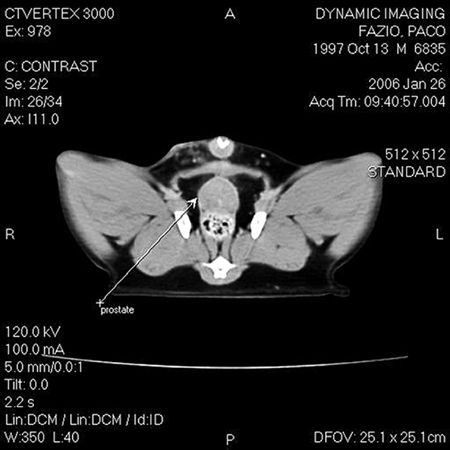

A 7-year-old intact male boxer was evaluated because of a preputial dermal mass that had been present for about one year.